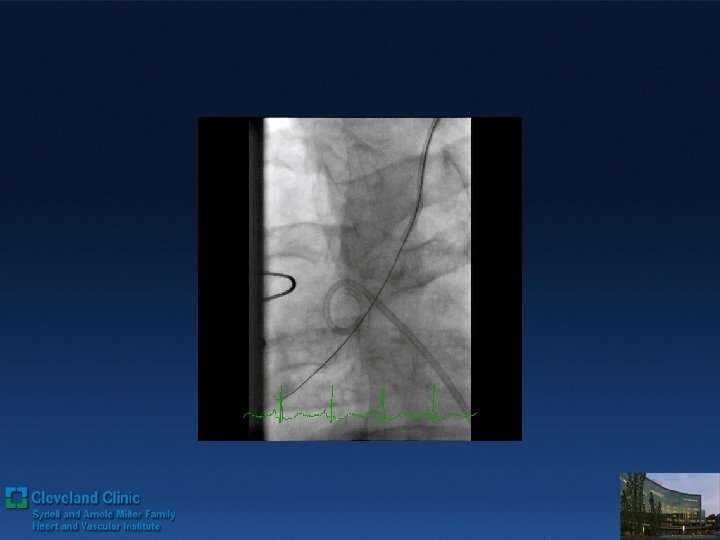

Direct Retrograde Crossing Retro grade wiring with wire trapping inside of ante grade Guide

Direct Retrograde Crossing Retro grade wiring with wire trapping inside of ante grade Guide 3 DES deployed